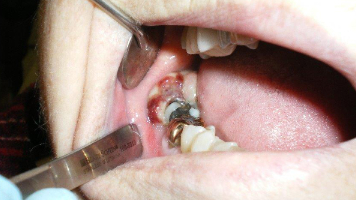

Removal of the lower third molars and the associated cystic lesions produced an expected histopathologic diagnosis of bilateral keratocystic odontogenic tumors. Because of the high suspicion of this diagnosis, surgery included aggressive removal of the lesions with peripheral ostectomy and treatment with Carnoy's solution.